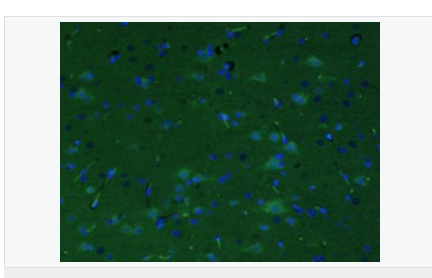

| 產(chǎn)品應(yīng)用 | ELISA=1:5000-10000 IHC-P=1:100-500 IHC-F=1:100-500 IF=1:200-800 (石蠟切片需做抗原修復(fù)) not yet tested in other applications. optimal dilutions/concentrations should be determined by the end user. |

| 產(chǎn)品介紹 | This gene encodes a member of the corticotropin-releasing factor family. The encoded preproprotein is proteolytically processed to generate the mature neuropeptide hormone. In response to stress, this hormone is secreted by the paraventricular nucleus (PVN) of the hypothalamus, binds to corticotropin releasing hormone receptors and stimulates the release of adrenocorticotropic hormone from the pituitary gland. Marked reduction in this protein has been observed in association with Alzheimer's disease. Autosomal recessive hypothalamic corticotropin deficiency has multiple and potentially fatal metabolic consequences including hypoglycemia and hepatitis. In addition to production in the hypothalamus, this protein is also synthesized in peripheral tissues, such as T lymphocytes, and is highly expressed in the placenta. In the placenta it is a marker that determines the length of gestation and the timing of parturition and delivery. A rapid increase in circulating levels of the hormone occurs at the onset of parturition, suggesting that, in addition to its metabolic functions, this protein may act as a trigger for parturition. [provided by RefSeq, Nov 2015] Function: This hormone from hypothalamus regulates the release of corticotropin from pituitary gland. Subunit: Interacts (via C-terminus) with CRFR1 (via N-terminal extracellular domain). Subcellular Location: Secreted. Similarity: Belongs to the sauvagine/corticotropin-releasing factor/urotensin I family. SWISS: P06850 Gene ID: 1392 Database links: Entrez Gene: 1392 Human Entrez Gene: 12918 Mouse Omim: 122560 Human SwissProt: P06850 Human SwissProt: Q8CIT0 Mouse Unigene: 75294 Human Unigene: 290689 Mouse Unigene: 10349 Rat Important Note: This product as supplied is intended for research use only, not for use in human, therapeutic or diagnostic applications. CRF陽性神經(jīng)元的胞體廣泛分布于下丘腦的室旁核、背縫核和藍(lán)斑核,這些區(qū)域也是去甲腎上腺素(NE)神經(jīng)元與5-羥色胺(5-HT)神經(jīng)元密集的區(qū)域。 CRF既具有神經(jīng)遞質(zhì)的性質(zhì)又具有神經(jīng)激素的性質(zhì)。CRF是聯(lián)系神經(jīng)系統(tǒng)與內(nèi)分泌系統(tǒng)的橋梁,在情感障礙疾患如焦慮和抑郁的發(fā)病中發(fā)揮重要作用. |